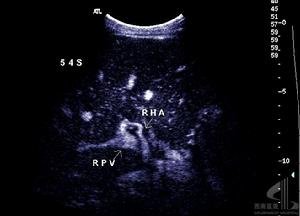

肝移植術1.3術後監測及數據形成計算出血患者移植術前終末期肝病模式(modelforend-stageliverdisease,MELD)評分,記錄腹腔出血患者術後每天腹腔引流液量(作為出血量),根據情況給予動態監測血常規、凝血情況(包括凝血酶原時間PT、國際標準化凝血時間INR、部分凝血活酶時間aPTT及纖維蛋白原Fbg),記錄移植術中及移植術後出血量(其中手術止血者包括手術中出血量及引流量)、輸血量,移植術中總入量、總出量和液體平衡量,並根據出入量計算術中和術後頭3天液體總平衡量。出血停止後給予行腹腔彩色超聲檢查明確腹腔積血及肝臟血運情況。

肝移植術2.2出血患者一般情況出血患者共10例,發病率11.5%(10/87);死亡4例,病死率40%(4/10)。基礎疾病分別為慢性B肝肝硬化合併肝癌(5例),慢性肝炎肝硬化合併肝性腦病(2例),慢性重型肝炎(2例),慢性肝炎肝硬化合併門脈高壓、脾功能亢進(1例)。其中採取保守治療5例,5例患者經保守治療後出血得到控制,其中1例治癒無併發症、4例並發MODS死亡,其中加用重組活化凝血因子Ⅶ者3例(其中1例出現肝動脈血栓);採取手術患者5例,其中用重組活化凝血因子Ⅶ者無效後手術者2例,手術時發現出血部位分別為膽管動脈吻合口處小動脈(2例)、手術區肝膽外的小動脈(2例)、肝動脈吻合口處小滋養動脈(1例),均治癒無其他併發症出現。

3.2手術因素包括未止血的痙攣血管解痙後出血,縫扎線松解、脫落後出血,供肝包膜血管及腹壁等血管未妥善止血,徹底止血後血栓脫落等,這種出血多為動脈性出血,一般靠補充血小板、凝血因子及凝血酶原等不能糾正,手術探察多可發現出血血管,需再手術治療。本研究中5例患者經補充血小板、凝血酶原等後不能糾正,而行剖腹探查術,而手術止血後徹底止血則屬此類,且手術中證實出血部位均為動脈,分別為膽管動脈吻合口處小動脈2例、手術區肝膽外的小動脈2例、肝動脈吻合口處小滋養動脈1例。